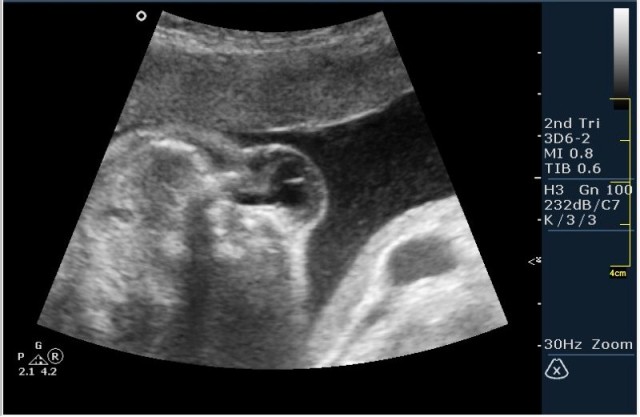

2.V-образное расщепление позвоночного столбы(рахисхизис)(на сонограмме №6 отчетливо виден дефект в поясничном отделе);

3.наличие дорсально расположенного содержимого спинномозгового канала(на сонограмме №7 видны мозговые оболочки).Это описывается как менингоцеле.

На сонограммах головы плода визуализаируется гифдроцефалия, патогенетически связанная со спинномозговой грыжей (менингомиелоцеле) представленная в 2D и 3D режимах. В режиме Skeleton не удалось получить "картинку презентационного качества", плод начал сильно вертется; но рекоммендация очень грамотная :idea: , спасибо за ваш пост!